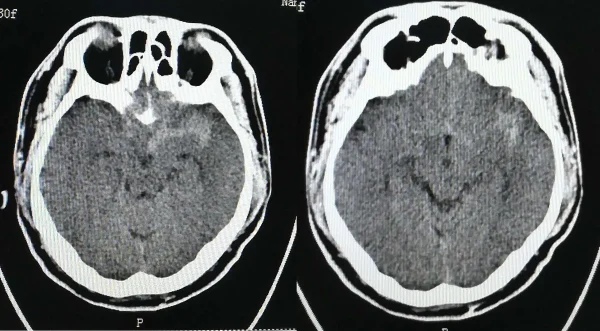

蛛网膜下腔出血和高血压是两种常见但严重的健康问题。蛛网膜下腔出血是一种紧急情况,通常由于脑内血管破裂引起,常见于老年人和高血压患者。根据患者的检查结果,发现其颈内动脉有动脉瘤,同时右侧肺和心脏也存在一些钙化斑。这些异常指标提示患者存在多种健康风险,需要进行进一步的治疗和监测。

通过上述检查结果可以推测出几个可能的疾病,包括蛛网膜下腔出血、颈内动脉动脉瘤和高血压。这些疾病不仅会对患者的生活质量造成严重影响,还有可能引发其他并发症。

蛛网膜下腔出血通常是由于脑动脉瘤破裂造成的。这种情况会导致脑内的血液渗入蛛网膜下腔,压迫脑组织,导致剧烈头痛、意识障碍和神经功能障碍。蛛网膜下腔出血的发病率较低,但一旦发生,致死率和致残率都很高。